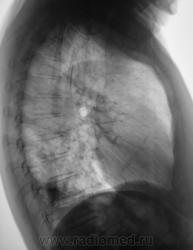

Пациент направлен на рентгенографию ОГК.

А томограмм нет. Просто демонстируется обызвествленная плевра.